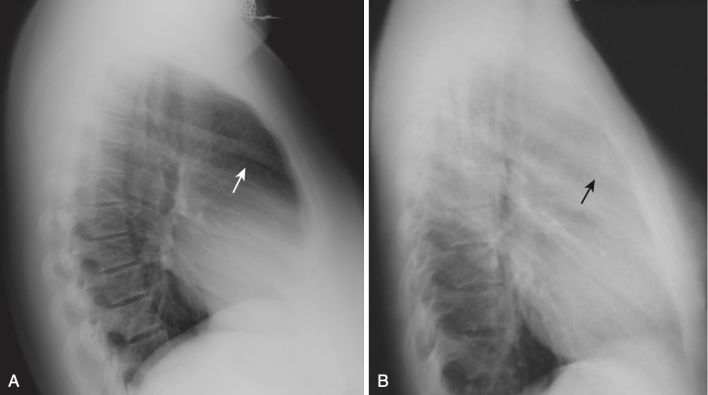

- Về khối u hạch ở trung thất, trên phim X quang thường có thể phát hiện với dấu hiệu lấp đầy khoảng trống sau xương ức. Bình thường, có một hình lưỡi liềm tương đối sáng ngay sau xương ức và phía trước bóng của động mạch chủ lên. Khi có một khối ở trung thất trước, khoảng trống sau xương ức bị lấp đầy . Bệnh lý hạch có lẽ là nguyên nhân thường gặp nhất làm che lấp khoảng sau xương ức (Hình 4). U tuyến ức, u quái (teratoma) và phì đại tuyến giáp dưới xương ức cũng có thể tạo ra các khối ở trung thất trước, nhưng chúng thường không có hình ảnh giống như hình trên.

Hình 4. Bệnh lý hạch (adenopathy) ở trung thất trước. A, Phim nghiêng bình thường thấy rõ khoảng sau xương ức (mũi tên trắng). B, Phim phổi nghiêng bên trái cho thấy mô mềm “lấp đầy” khoảng trống bình thường phía sau xương ức (mũi tên đen). Dấu hiệu này thể hiện bệnh lý hạch lympho ở trung thất trước ở một bệnh nhân bị lymphoma.